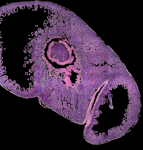

Still image of KESM data (H&E stained mouse gut) -1